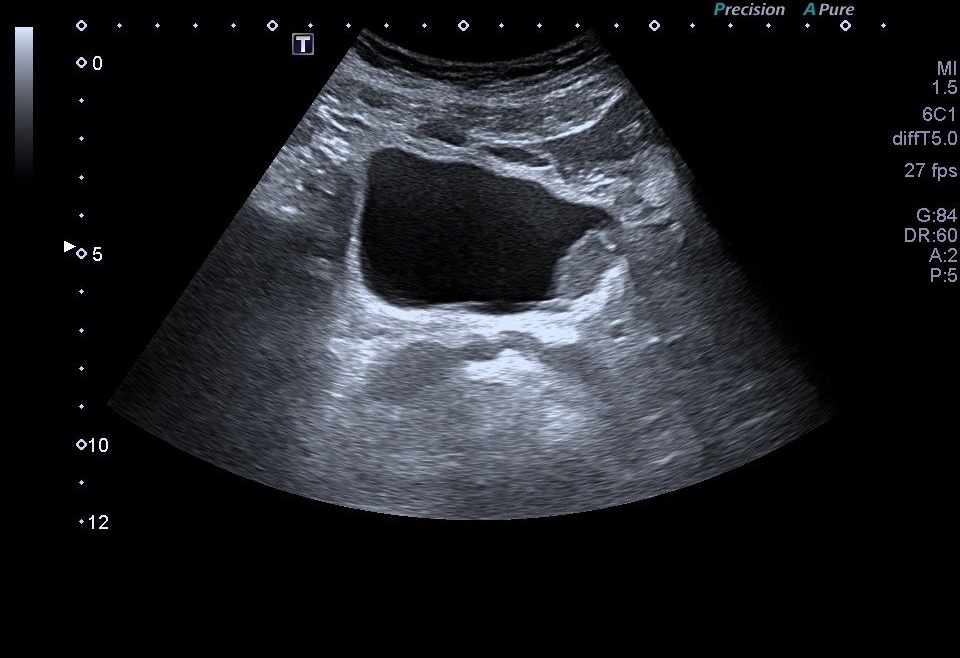

Al realizar una ecografía reno vesical, los hallazgos ecográficos típicos del urotelioma incluyen la visualización de una masa sólida en la vejiga.

Esta masa puede presentar una apariencia heterogénea, con áreas hipoecoicas (menos ecogénicas) y áreas hiperecoicas (más ecogénicas) en relación con el tejido circundante. Además, puede observarse un crecimiento intraluminal, lo que significa que la masa se proyecta hacia el interior de la vejiga.

- Ubicación: El urotelioma generalmente se encuentra en la mucosa o submucosa de la vejiga. Puede presentarse como una lesión focal o múltiple.

- Apariencia ecográfica: El urotelioma se muestra como una masa sólida con una ecogenicidad variable en comparación con el tejido circundante. Puede presentar áreas hipoecoicas (menos ecogénicas) y áreas hiperecoicas (más ecogénicas).

- Contornos: Los contornos de la masa pueden ser irregulares y asimétricos. Pueden observarse proyecciones intraluminales, lo que indica que la masa se extiende hacia el interior de la vejiga.

- Estructura interna: La estructura interna del urotelioma puede ser heterogénea debido a la presencia de áreas de necrosis o hemorragia. Estas áreas pueden ser identificadas por su apariencia hipoecoica o hiperecoica respectivamente.También calcificiones…como es el caso que nos ocupa hoy.